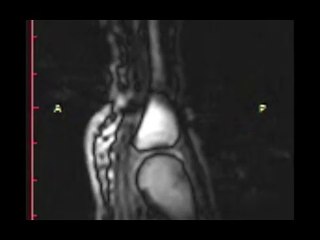

University of Southern California researchers took real-time MRIs of beatboxers working their magic. all in the name of science.